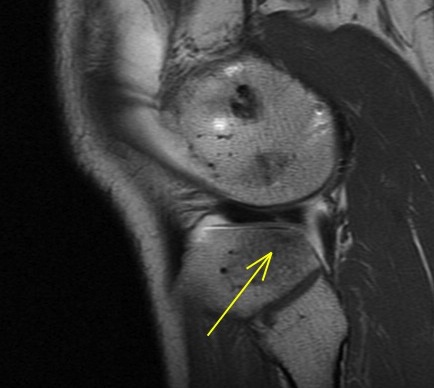

Figure 1 for case Lateral meniscus flap tear and adjacent stress fracture

Figure 1

Knee arthrogram showing lateral meniscus flap tear and adjacent stress fracture.

Lateral meniscus flap tear and adjacent stress fracture